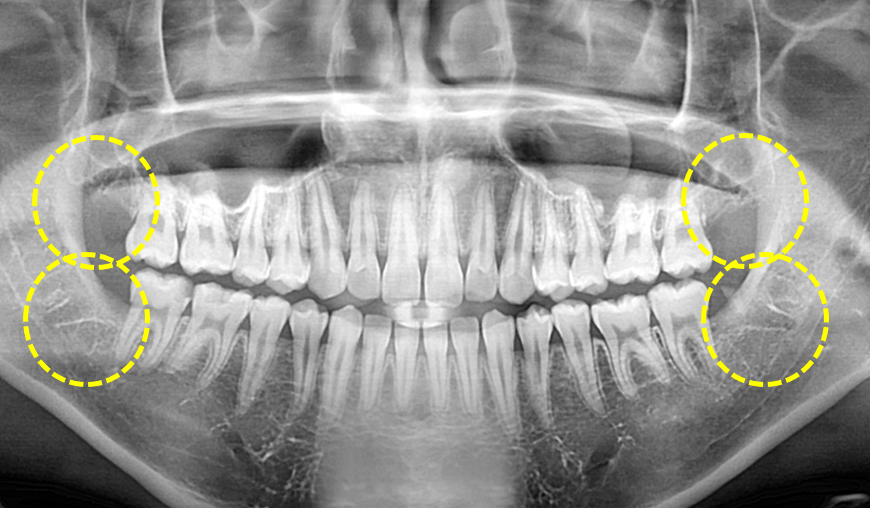

양측 상,하악 사랑니 발치.

After

보통은 한쪽 위, 아래 사랑니를 먼저 발치하고

어느정도 치유가 이루어지면 반대편 위, 아래 사랑니를 발치하는 것이

저작과 음식물 섭취에 오는 불편을 최소화 해줄 수 있습니다.